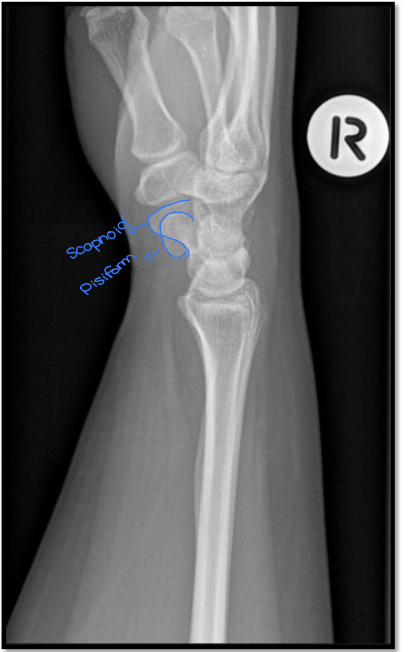

What is the positioning fault?

• scapholunate joint is closed (obliqued)

• trapezoid and trapezium are seperated

• thumb is away from IR